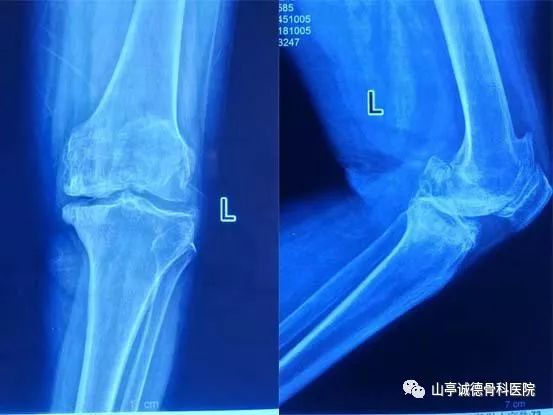

術(shù)前X線片可見左側(cè)骨質(zhì)增生明顯